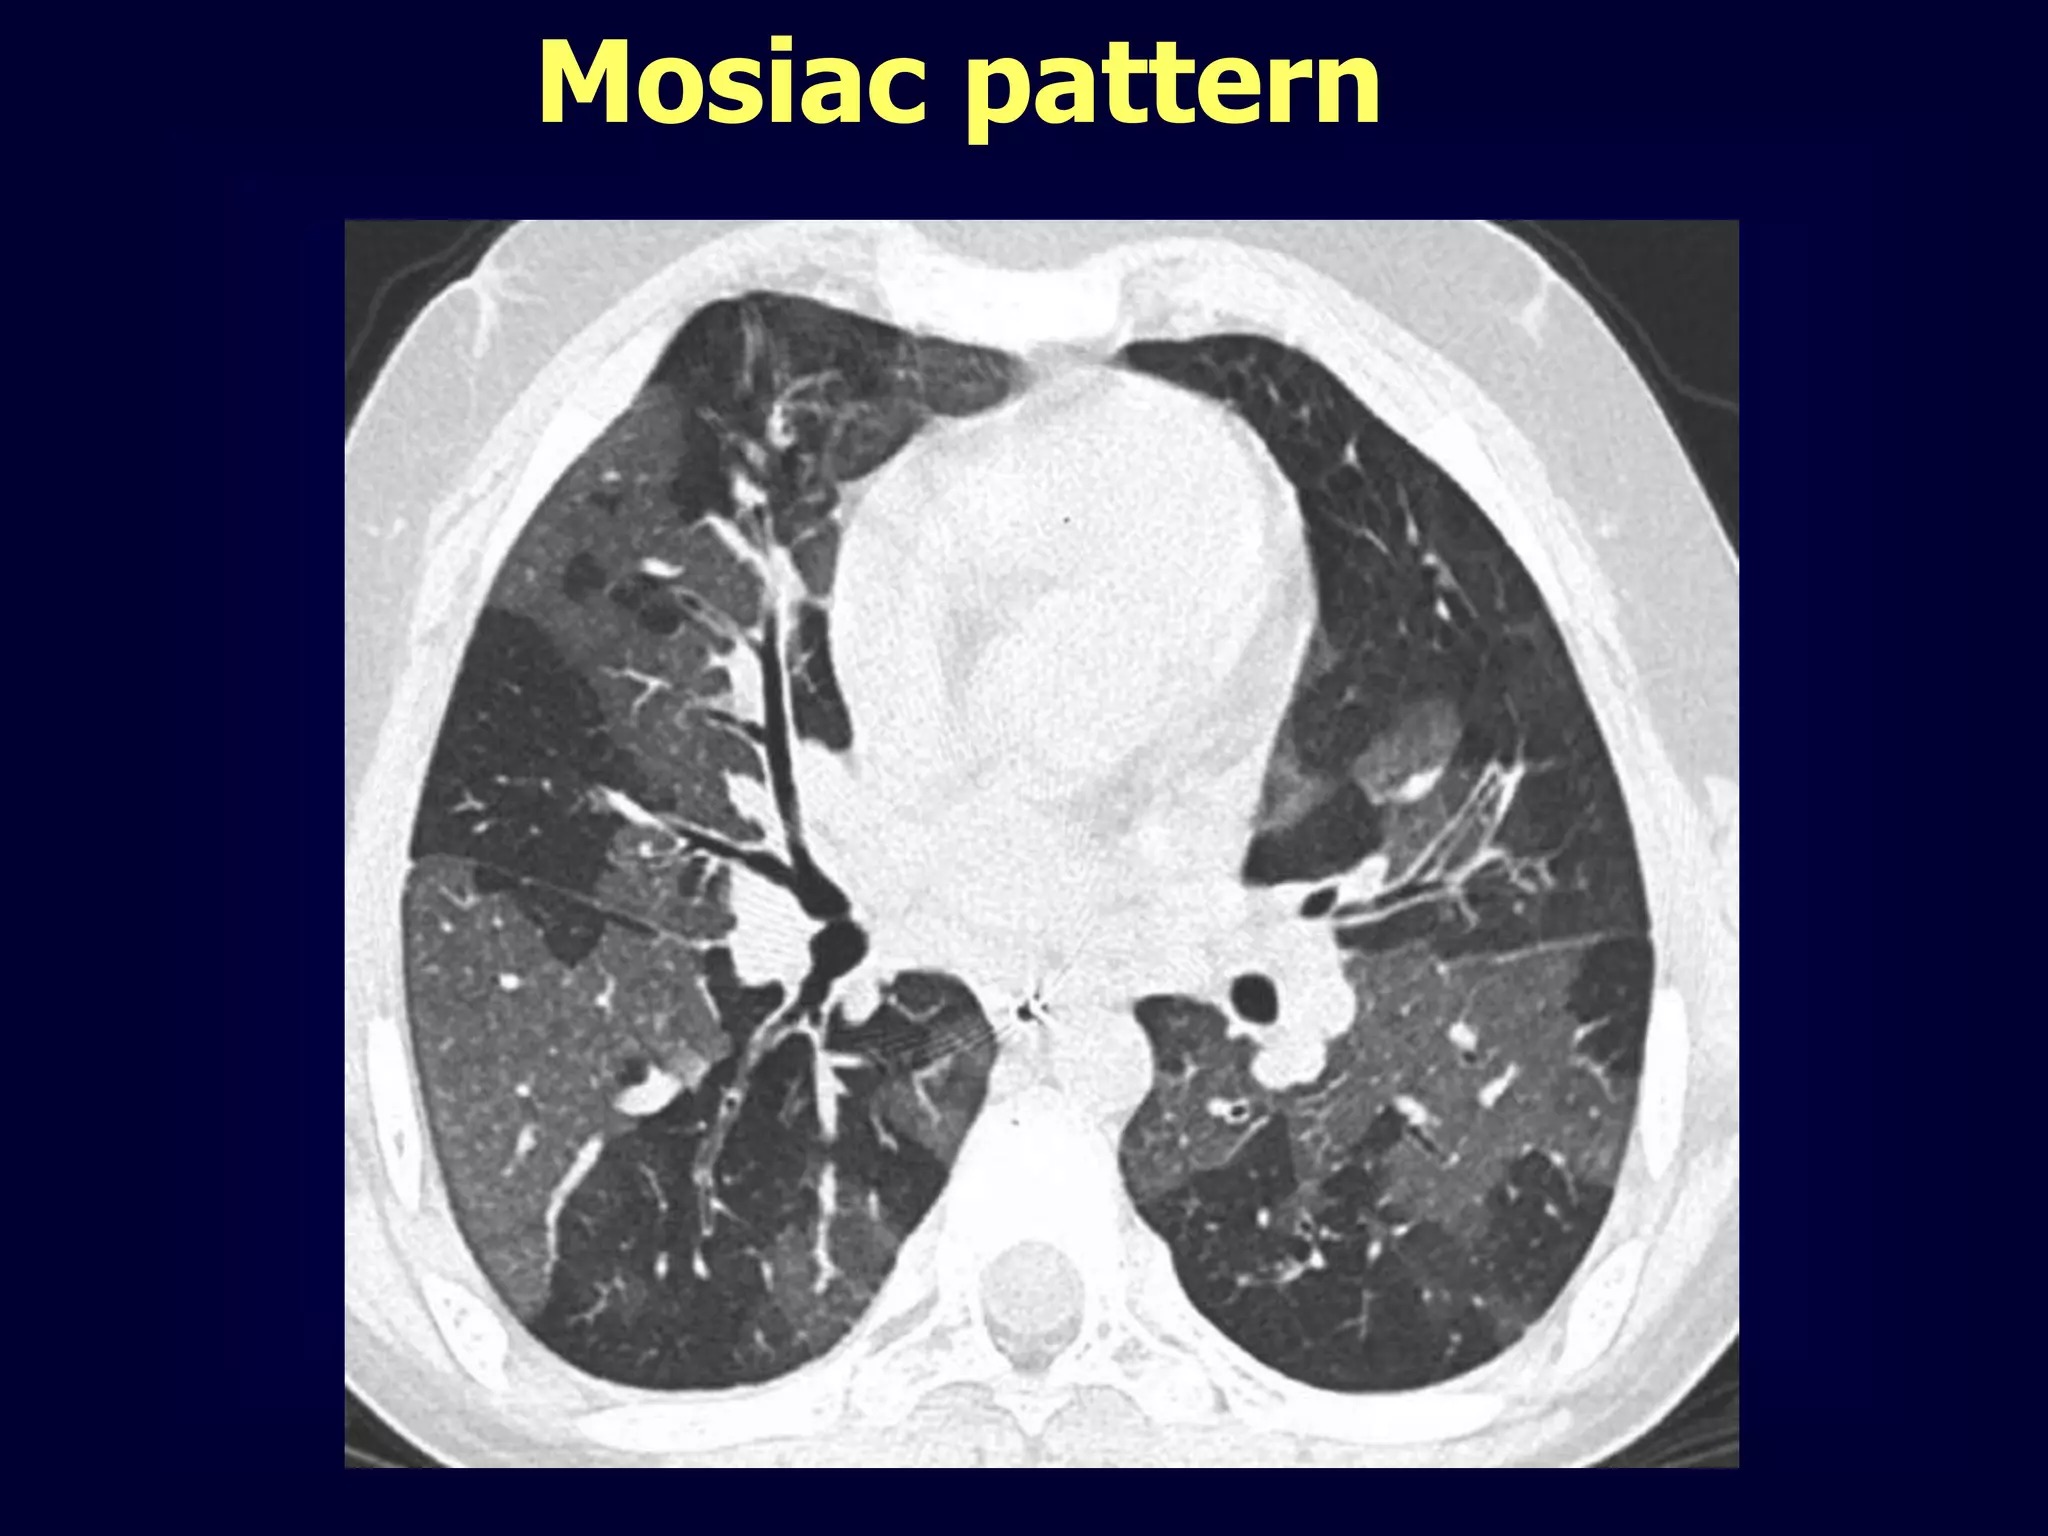

Mosiac pattern

Where is the pathology ???????

in the areas with increased density

meaning there is ground glass

in the areas with decreased density

meaning there is air trapping

Pathology in black areas

Airtrapping: Airway

Disease

Bronchiolitis obliterans (constrictive bronchiolitis)

idiopathic, connective tissue diseases, drug reaction,

after transplantation, after infection

Hypersensitivity pneumonitis

granulomatous inflammation of bronchiolar wall

Sarcoidosis

Asthma / Bronchiectasis / Airway diseases